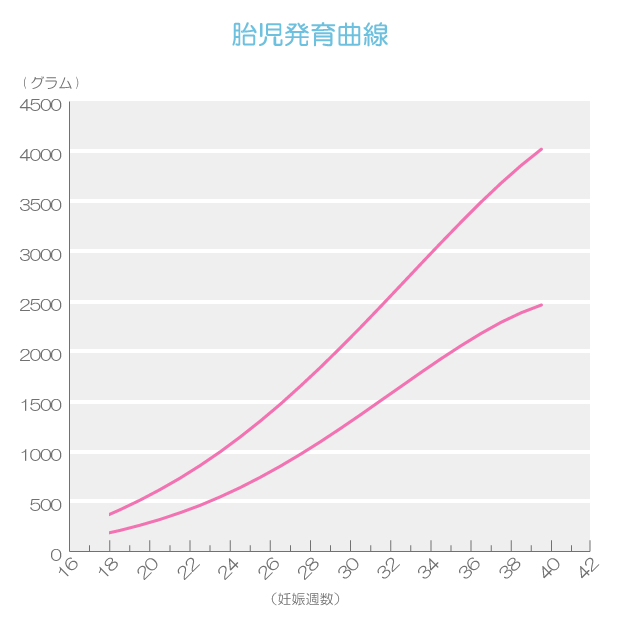

母子手帳「胎児発育曲線 新生児の成長曲線 」の見方と活用法-おむつのムーニー 公式 ユニ・チャーム。

医師監修 胎児の発育曲線 成長曲線 とは?どのように見ればいいの?ゼクシィBaby。

胎児発育曲線ギリギリ成長の小ささで16週から34週まで育ってるべびお君。 - 保育士うたのサイト。

胎児発育曲線』とは?週ごとの発育の目安を助産師が解説◎ - 株式会社エバーセンス。

胎児発育曲線』とは?週ごとの発育の目安を助産師が解説◎ - 株式会社エバーセンス。

胎児発育曲線の±2.0SDの意味は?エコー写真に学ぶ統計学 - 日常を少し掘り下げてみる。

医師監修 おなかの赤ちゃんの発育は順調? 「胎児発育曲線」とはトモニテ。

胎児発育曲線の±2.0SDの意味は?エコー写真に学ぶ統計学 - 日常を少し掘り下げてみる。

母子手帳「胎児発育曲線 新生児の成長曲線 」の見方と活用法-おむつのムーニー 公式 ユニ・チャーム。